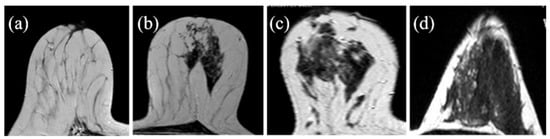

The operators’ assessments of FGT were carried out on the T2 morphological sequences and the first post-contrast acquisition of the dynamic sequence; otherwise, BPE evaluations were carried out on the first post-gadolinium dynamic sequence, as based on the literature [23,34]. FGT and BPE were classified according to ACR BIRADS [7] criteria in four groups: FGT in almost entirely fat (a), scattered fibro glandular tissue (b), heterogeneous fibro glandular tissue (c), extreme fibro glandular tissue (d), and BPE in minimal (I), mild (II), moderate (III), marked (IV), symmetric, or asymmetric. Examples of this classification are shown in Figure 1 and Figure 2.

Figure 1. Fibroglandular tissue (FGT): (a)almost entirely fat; (b) scattered fibroglandular tissue; (c) heterogeneous fibroglandular tissue; (d) extreme fibroglandular tissue.